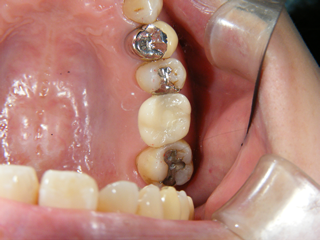

口腔内診査、レントゲン、CTなどから、骨量は十分と判断し歯肉を開かずに埋め込みすることになりました。

歯肉を開いていないので、出血もなく縫っていません。

1本の埋め込みなら、15分程度で終了します。この状態で3~4ヶ月待ちます。